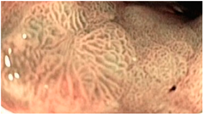

| Gastric Mucosal Pattern Category | NBI-CE Example Image |

|---|---|

| Normal round | ![]() |

| Normal mosaic and polygonal | ![]() |

| Enlarged mosaic and polygonal | ![]() |

| Tubulo-villous | ![]() |